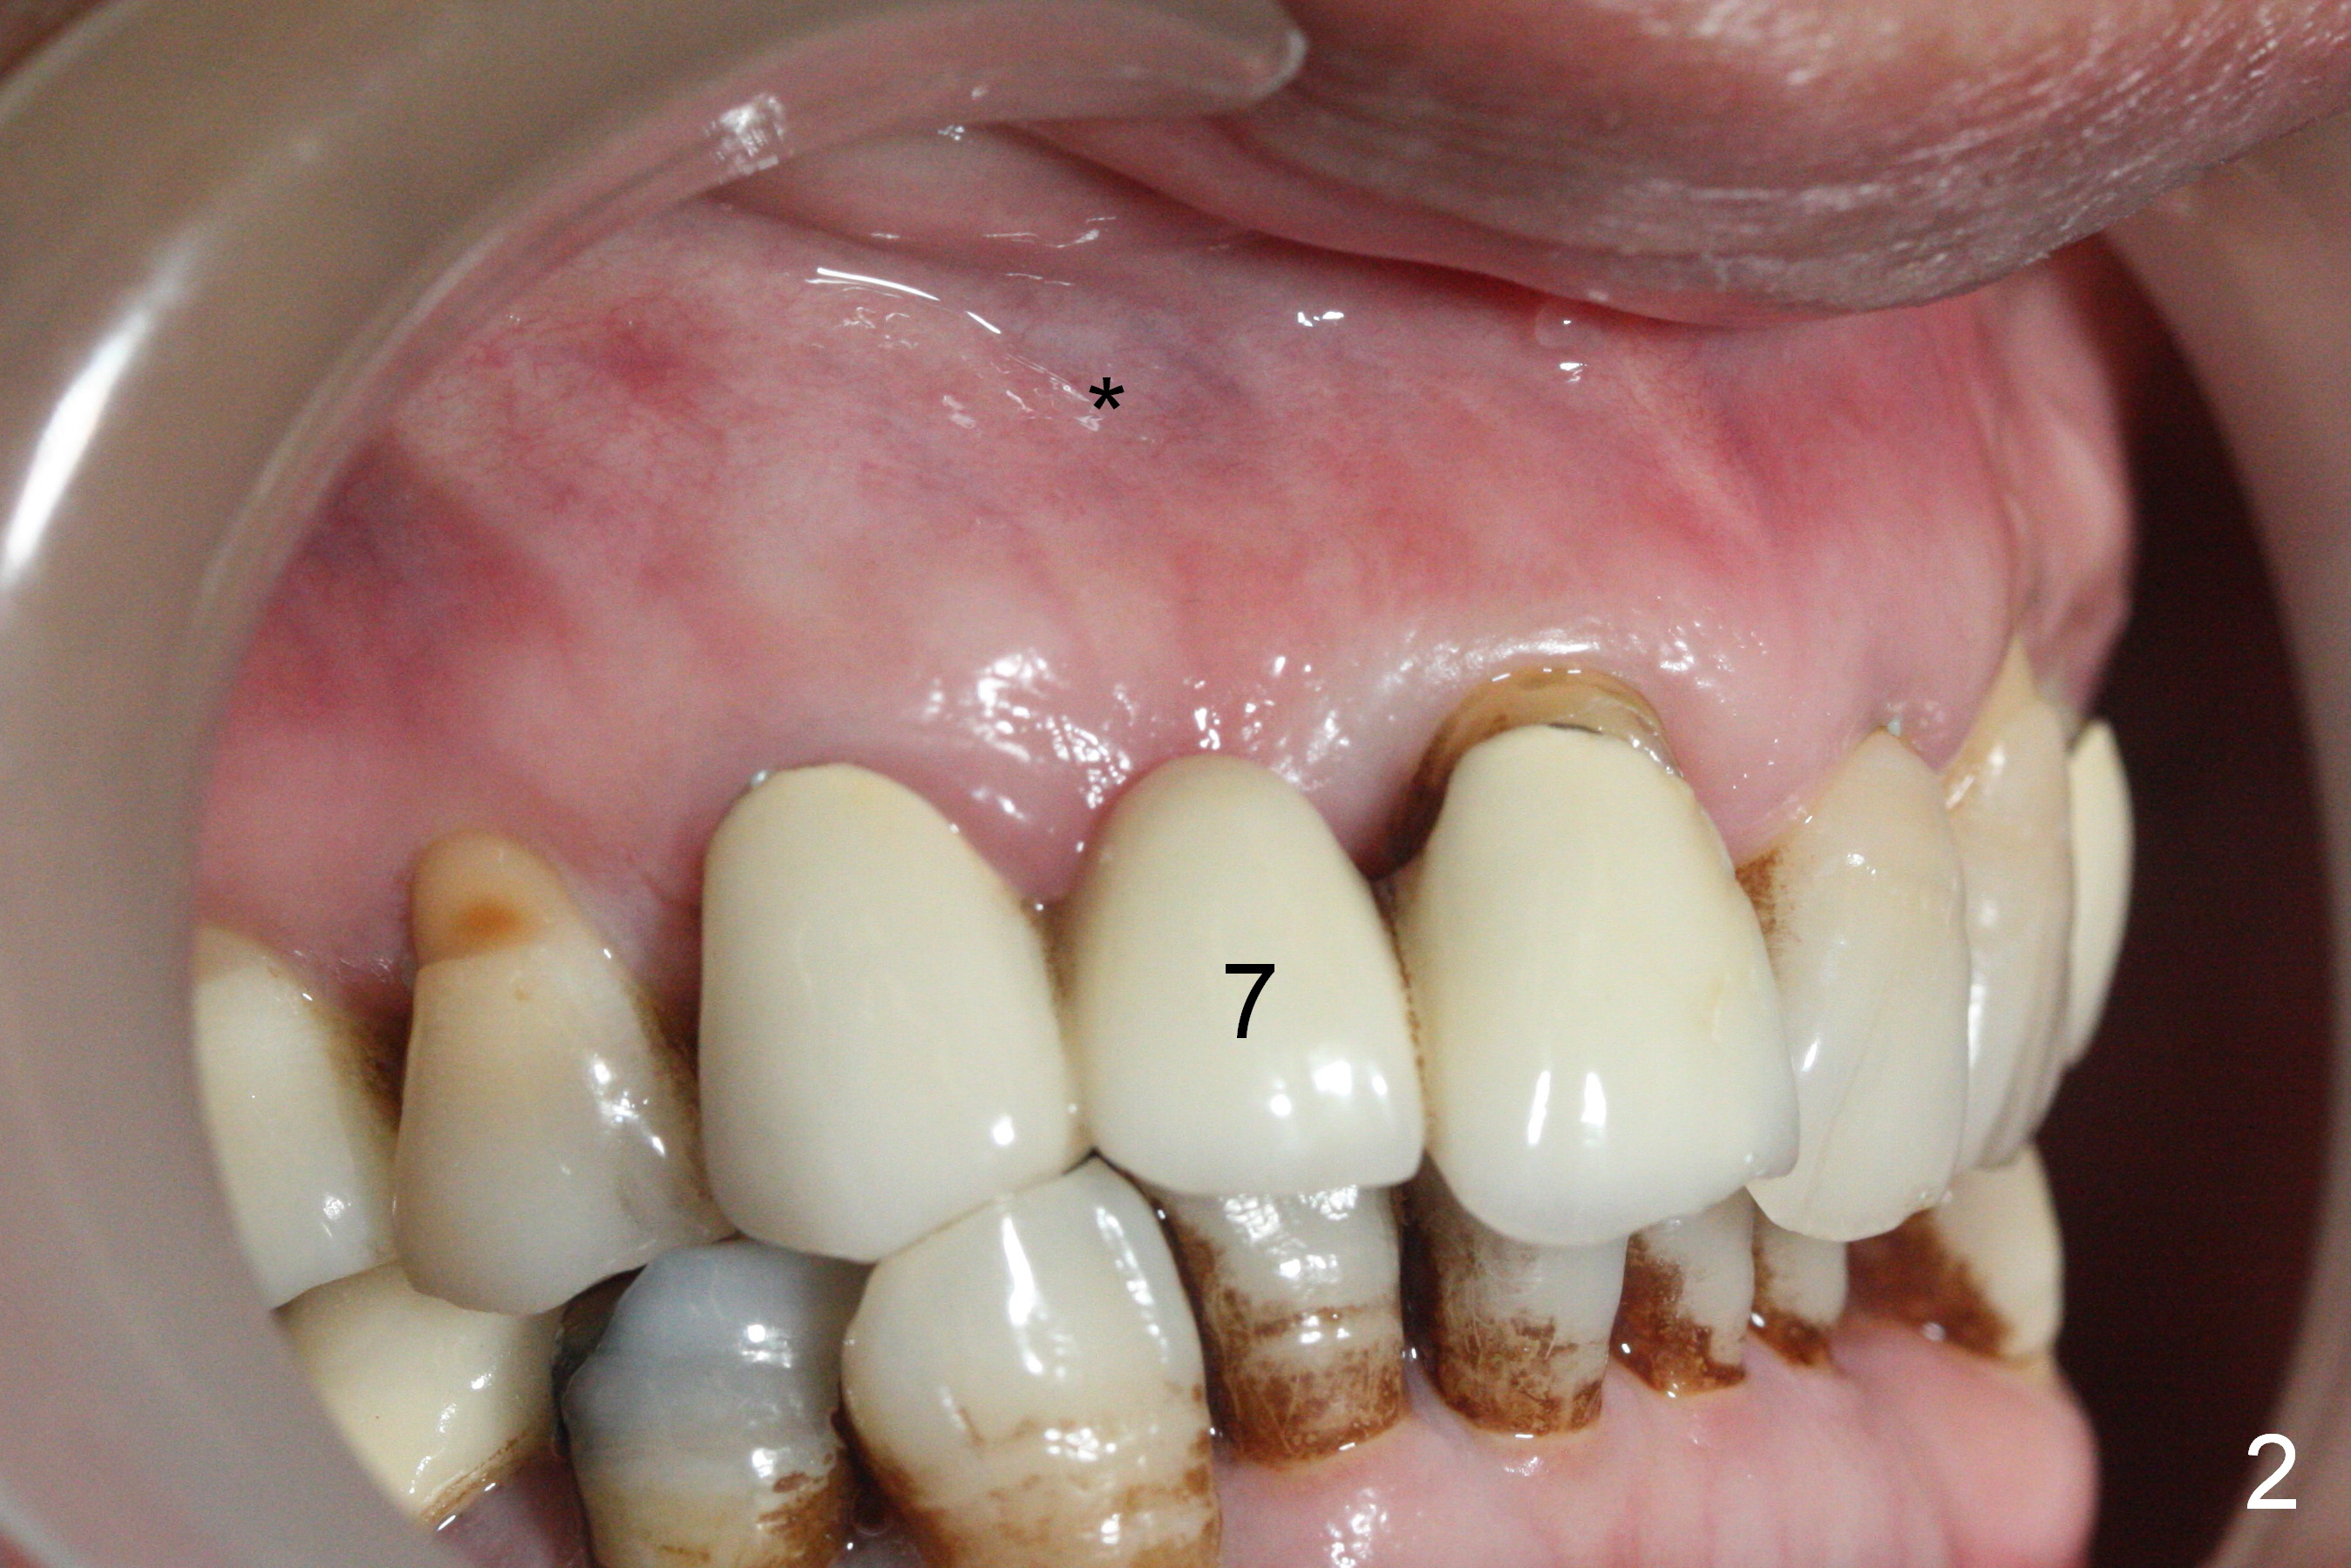

A 43-year-old woman has poor dentition including the tooth #5 (Fig.1) for RCT (Fig.3) and the teeth #2, 30 and 31 are missing.  The retainer at #6 fractures (Fig.1 *).  After sectioning the bridge between #7 and 8, fabricate prefabricated post at #6 if the latter is salvageable.  Otherwise extract (Clindamycin) and implant (Fig.3).  Anyway, a 3-mm or smaller one-piece implant is to be placed at #7 for stability and retention.  Pay attention to the labial concavity at #7 (Fig.2 *).  Surgical stent has been made.